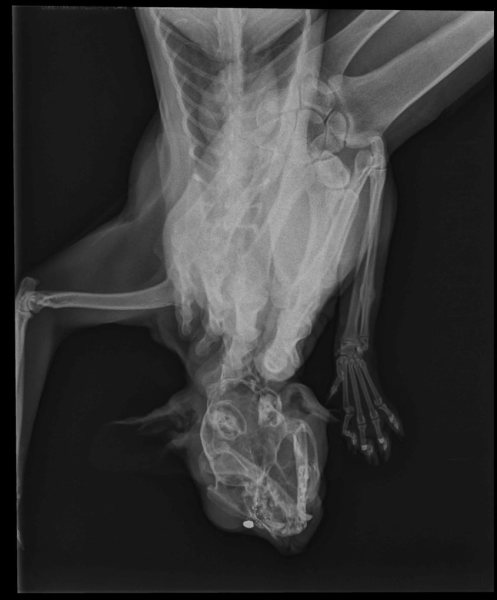

Fisia, kotka Bartłomieja Karcza została postrzelona aż dwa razy.

Niestety, 10 stycznia ponownie ktoś strzelał do Fisi.

- Tym razem przyszła z rannym noskiem – opowiada pan Bartłomiej. - Widać było, że pocisk trafił w jej nos i utknął w głowie. W naszym powiecie nikt nie chciał się podjąć operacji, dlatego pojechałem z kotką do kliniki w Warszawie. Tam uratowano jej życie, ale śrutu nie udało się wyciągnąć z głowy. Będzie tam tkwił prawdopodobnie do końca jej życia.